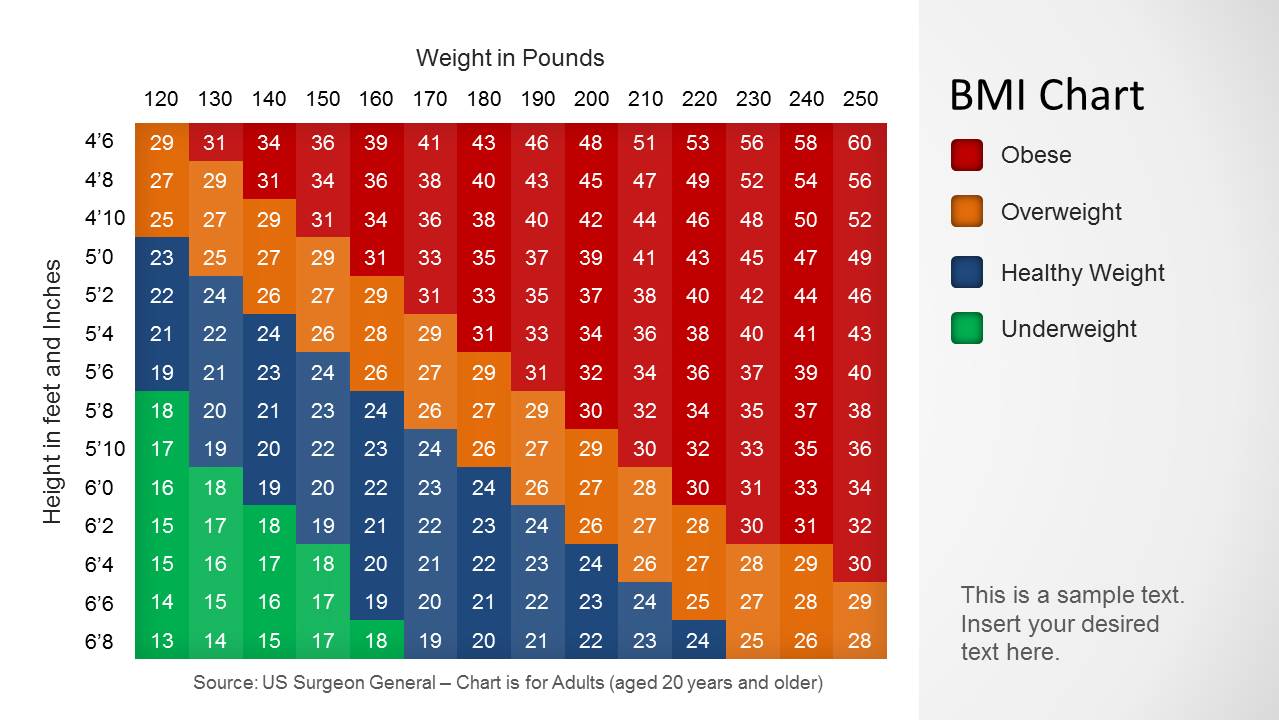

Torso Anatomy Chart / Torso Anatomy Chart : Anatomy Chart Trigger Point Charts - Paka Lapan  Pin by sindo vazquez on Anatomia dibujo | Anatomy sketches, Anatomy drawing, Human anatomy art